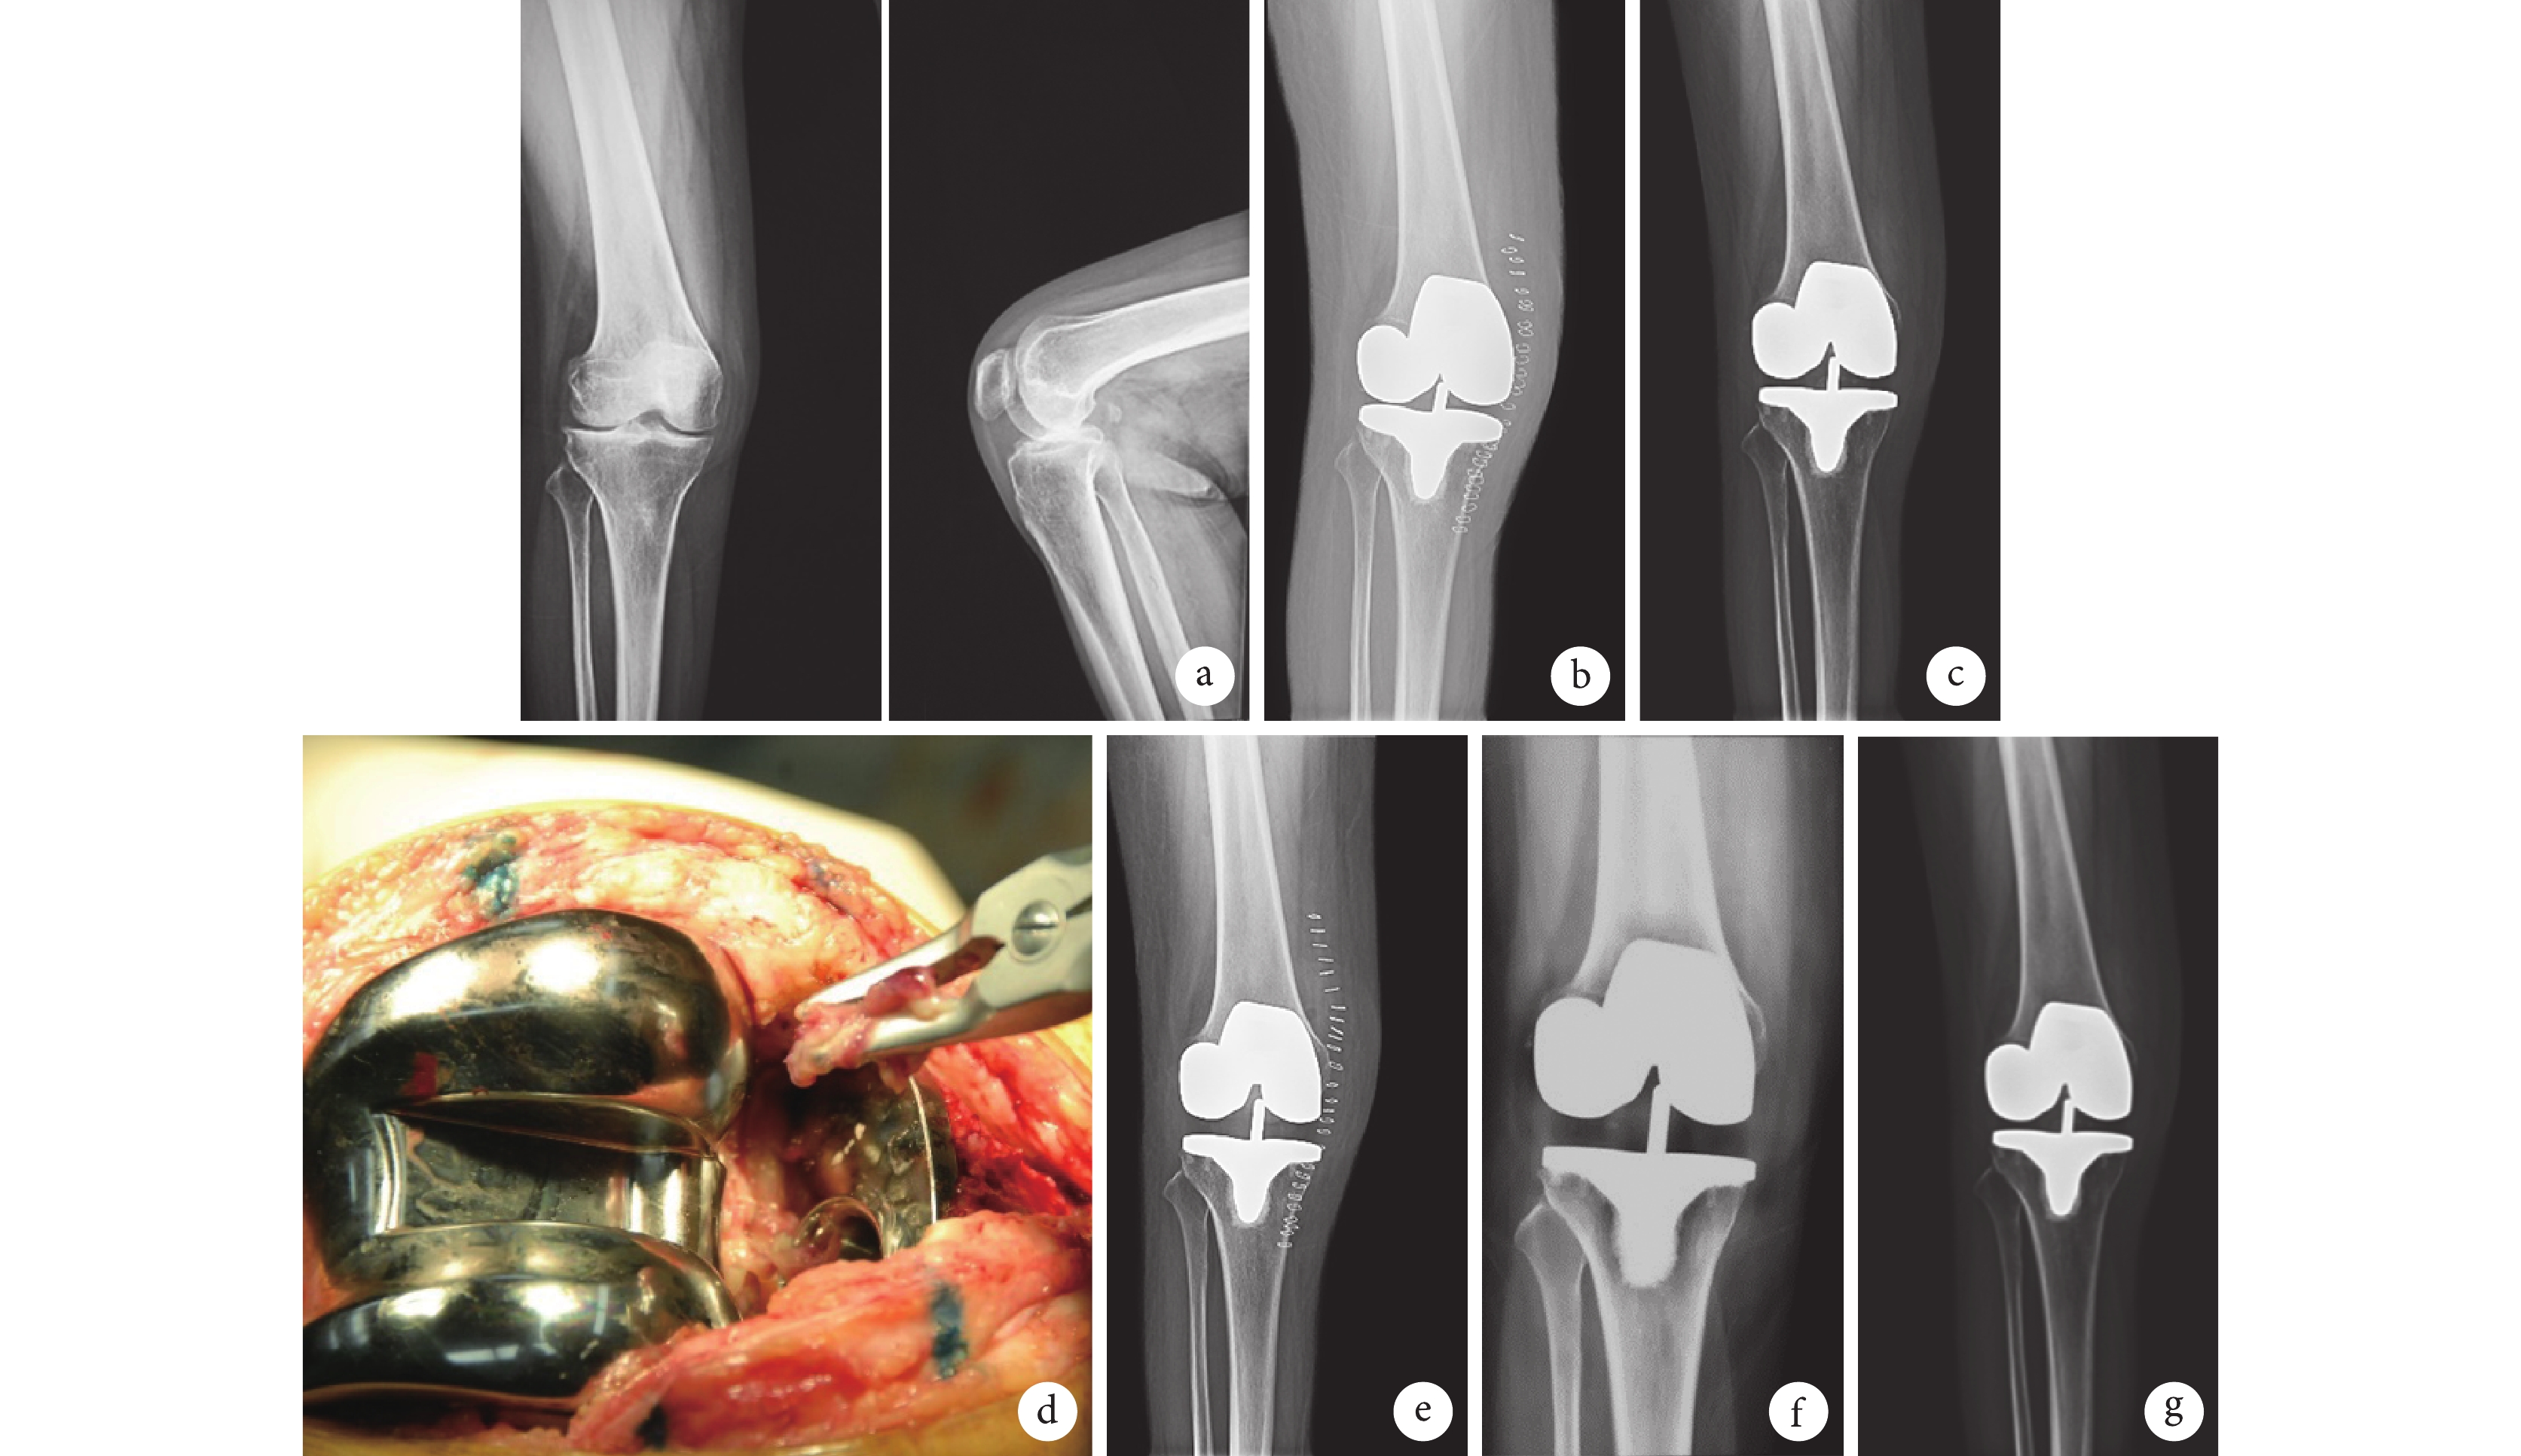

末次隨訪時,THA 患者髖關節 Harris 評分為(81.4±19.1)分,TKA 患者膝關節 HSS 評分為(76.9±11.8)分,均明顯高于術前,差異有統計學意義(t=9.917,P=0.000;t=14.035,P=0.000)。X 線片復查示,除治療失敗者外,其余患者假體無松動、下沉。見圖 2。

a. 初次置換術前膝關節正側位 X 線片;b. 初次置換術后第 2 天膝關節正位 X 線片;c. 初次置換術后 7 個月(保留假體清創術前)膝關節正位 X 線片;d. 術中清除假體周圍炎性組織;e. 保留假體清創術后即刻膝關節正位 X 線片;f. 保留假體清創術后 1 年膝關節正位 X 線片;g. 保留假體清創術后 3 年正位 X 線片

Figure2. A 60-year-old female patient with PJI at 7 months after TKAa. Anteroposterior and lateral X-ray films before primary TKA; b. Anteroposterior X-ray film at 2 days after primary TKA; c. Anteroposterior X-ray film at 7 months after primary TKA (before debridement); d. Debriding necrotic and infected tissue surrounding the implant during operation; e. Anteroposterior X-ray film at immediate after debridement; f. Anteroposterior X-ray film at 1 year after debridement; g. Anteroposterior X-ray film at 3 years after debridement